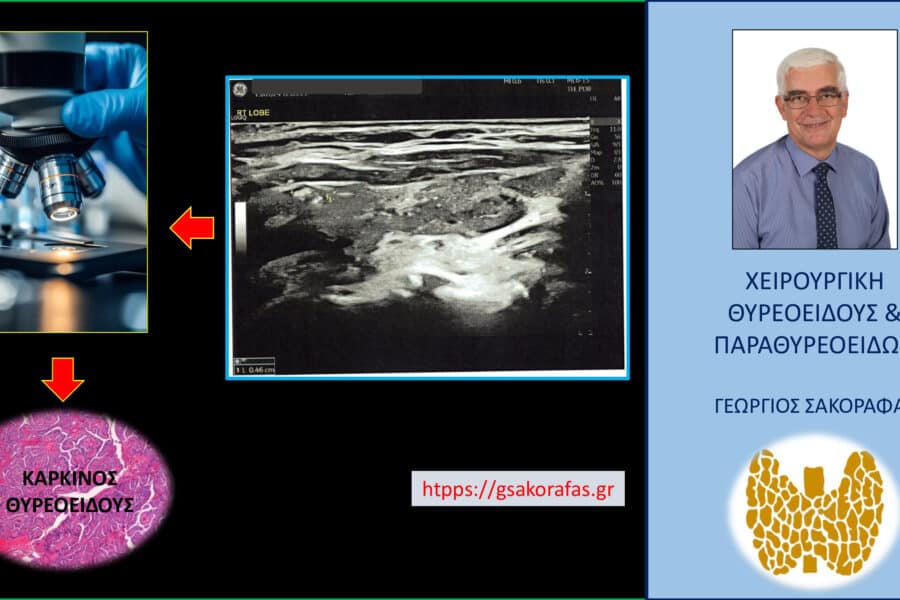

Όζοι θυρεοειδούς και συμπληρωματική θυρεοειδεκτομή (completion thyroidectomy) – με αφορμή ασθενή μας Παρουσίαση ασθενούς Αιτία…